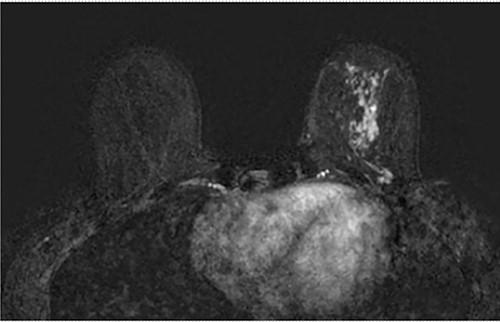

A 37-year-old Caucasian woman underwent a left therapeutic skin-sparing mastectomy and sentinel lymph node biopsy and a simultaneous right risk-reducing skin-sparing mastectomy in 2016. She had bilateral immediate subpectoral breast reconstruction with Becker-35 expandable implants combined with SurgiMend® (Integra LifeSciences, Princeton, NJ) acellular dermal matrix (ADM). Histology revealed 45 mm of high-grade ductal carcinoma in situ (DCIS) with three foci of invasive carcinoma No Special Type (NST) measuring 4, 2 and 1.6 mm in size (Fig. 1). The disease was ER positive, PR-negative and HER-2 negative, the two sentinel nodes were disease-free and the patient received tamoxifen as adjuvant therapy.

Axial fat-saturated post contrast Magnetic Resonance Imaging (MRI) of the breasts. There is extensive stippled non mass like enhancement throughout the inferior and central left breast with type 1 benign kinetics in keeping with DCIS.